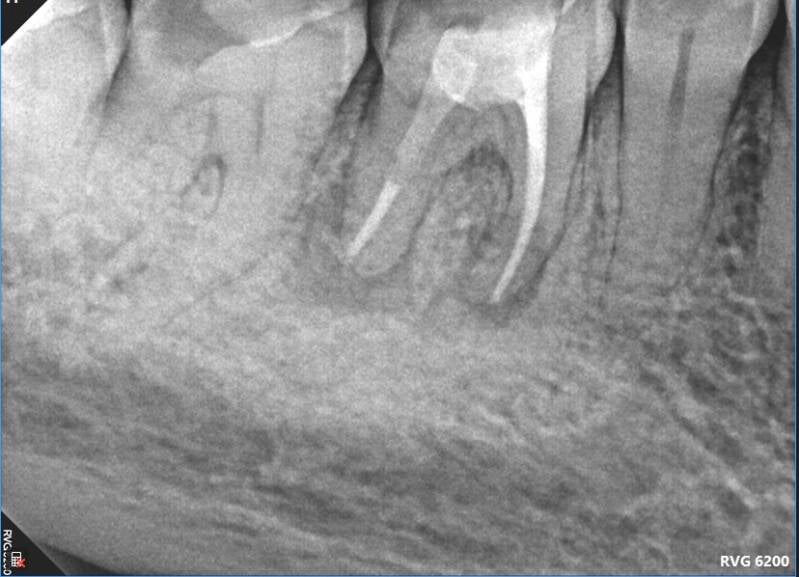

Case: RCT on Tooth #30

54-year-old female, osteoporosis (on oral bisphosphonate therapy), no known allergies.

Dx: Pulp necrosis and asymptomatic apical periodontitis.

Tx: Non-surgical root canal therapy (RCT).

Reflection

Given the patient's long-term bisphosphonate use (>5 years), root canal therapy was selected over extraction to minimize MRONJ risk, despite limited restorability. Treatment was complicated by a highly calcified and merging mesial root system. Patient remained asymptomatic and successfully proceeded with post and core buildup after two months.